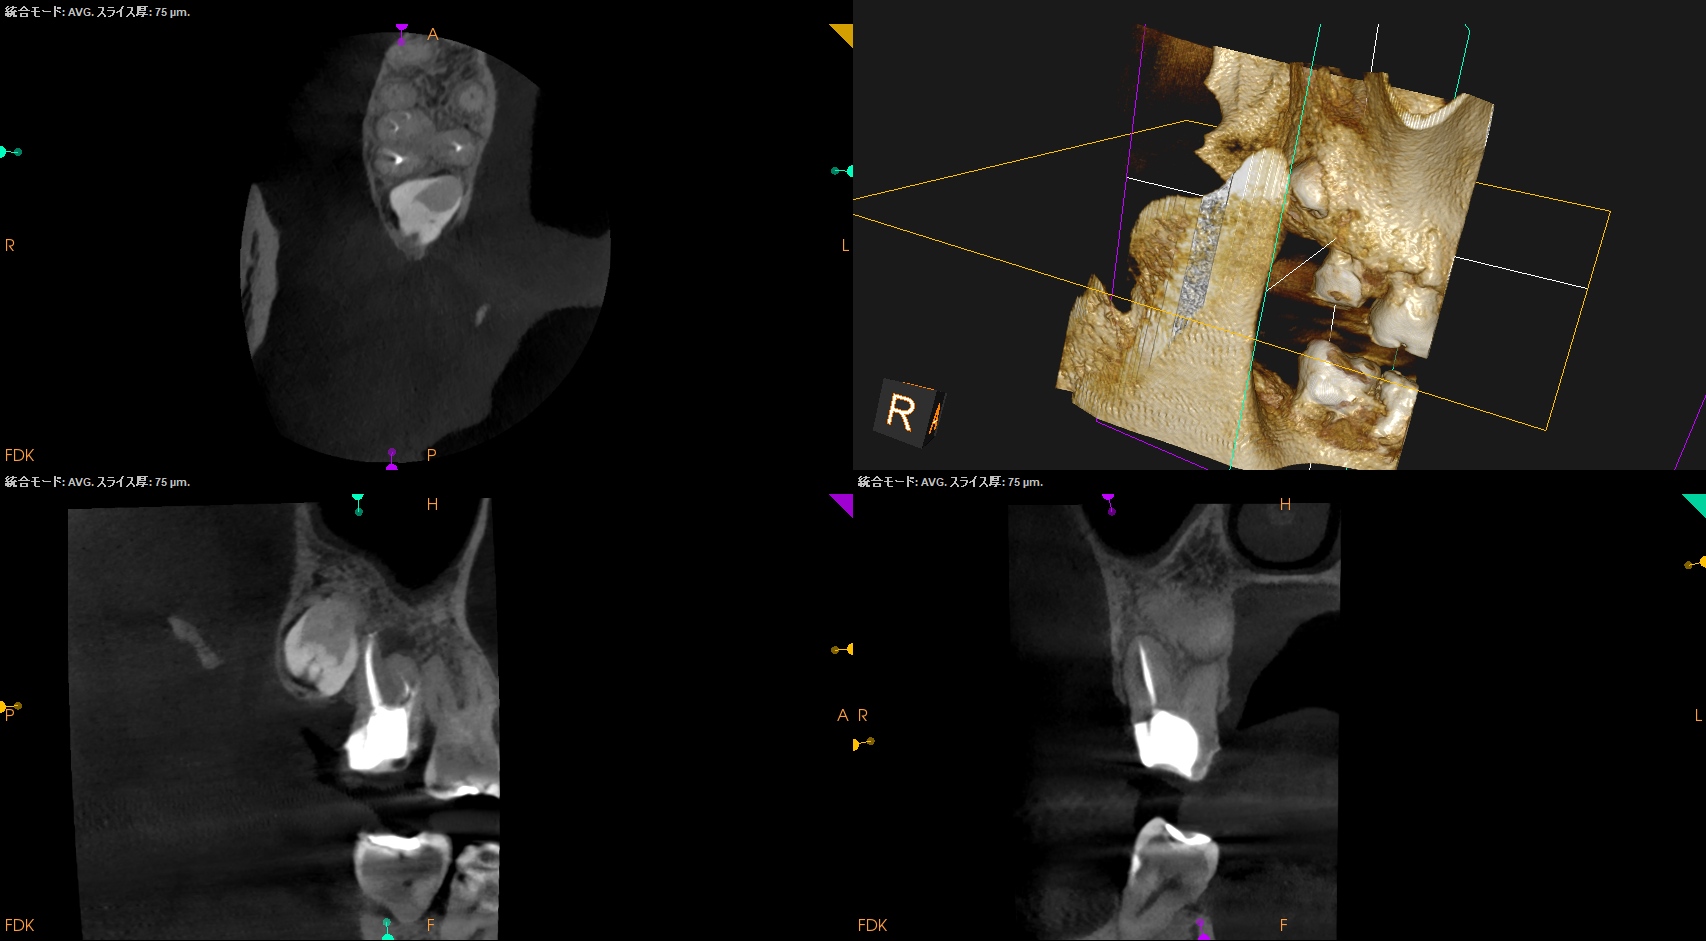

☆Intentional Replantation時に再植行為が難しい場合の臨床的対応方法

1. Tooth Sloothで歯牙を患者さんに咬合させて元の位置に戻す

2. それでも再植が難しければ、抜歯窩の歯牙を再植する上でアンダーカットになっている部分(分岐部, 頬舌側・近遠心部分の歯牙のアンダーカット部分)の歯槽骨を除去する

すると抜歯窩へ戻すことができた。

術後にPAを撮影した。

MB

DB

P

問題はないだろう。

この1ヶ月後に経過観察で来院された。

#2 Intentional Replantation 1M recall(2026.1.28)

次回は半年後である。